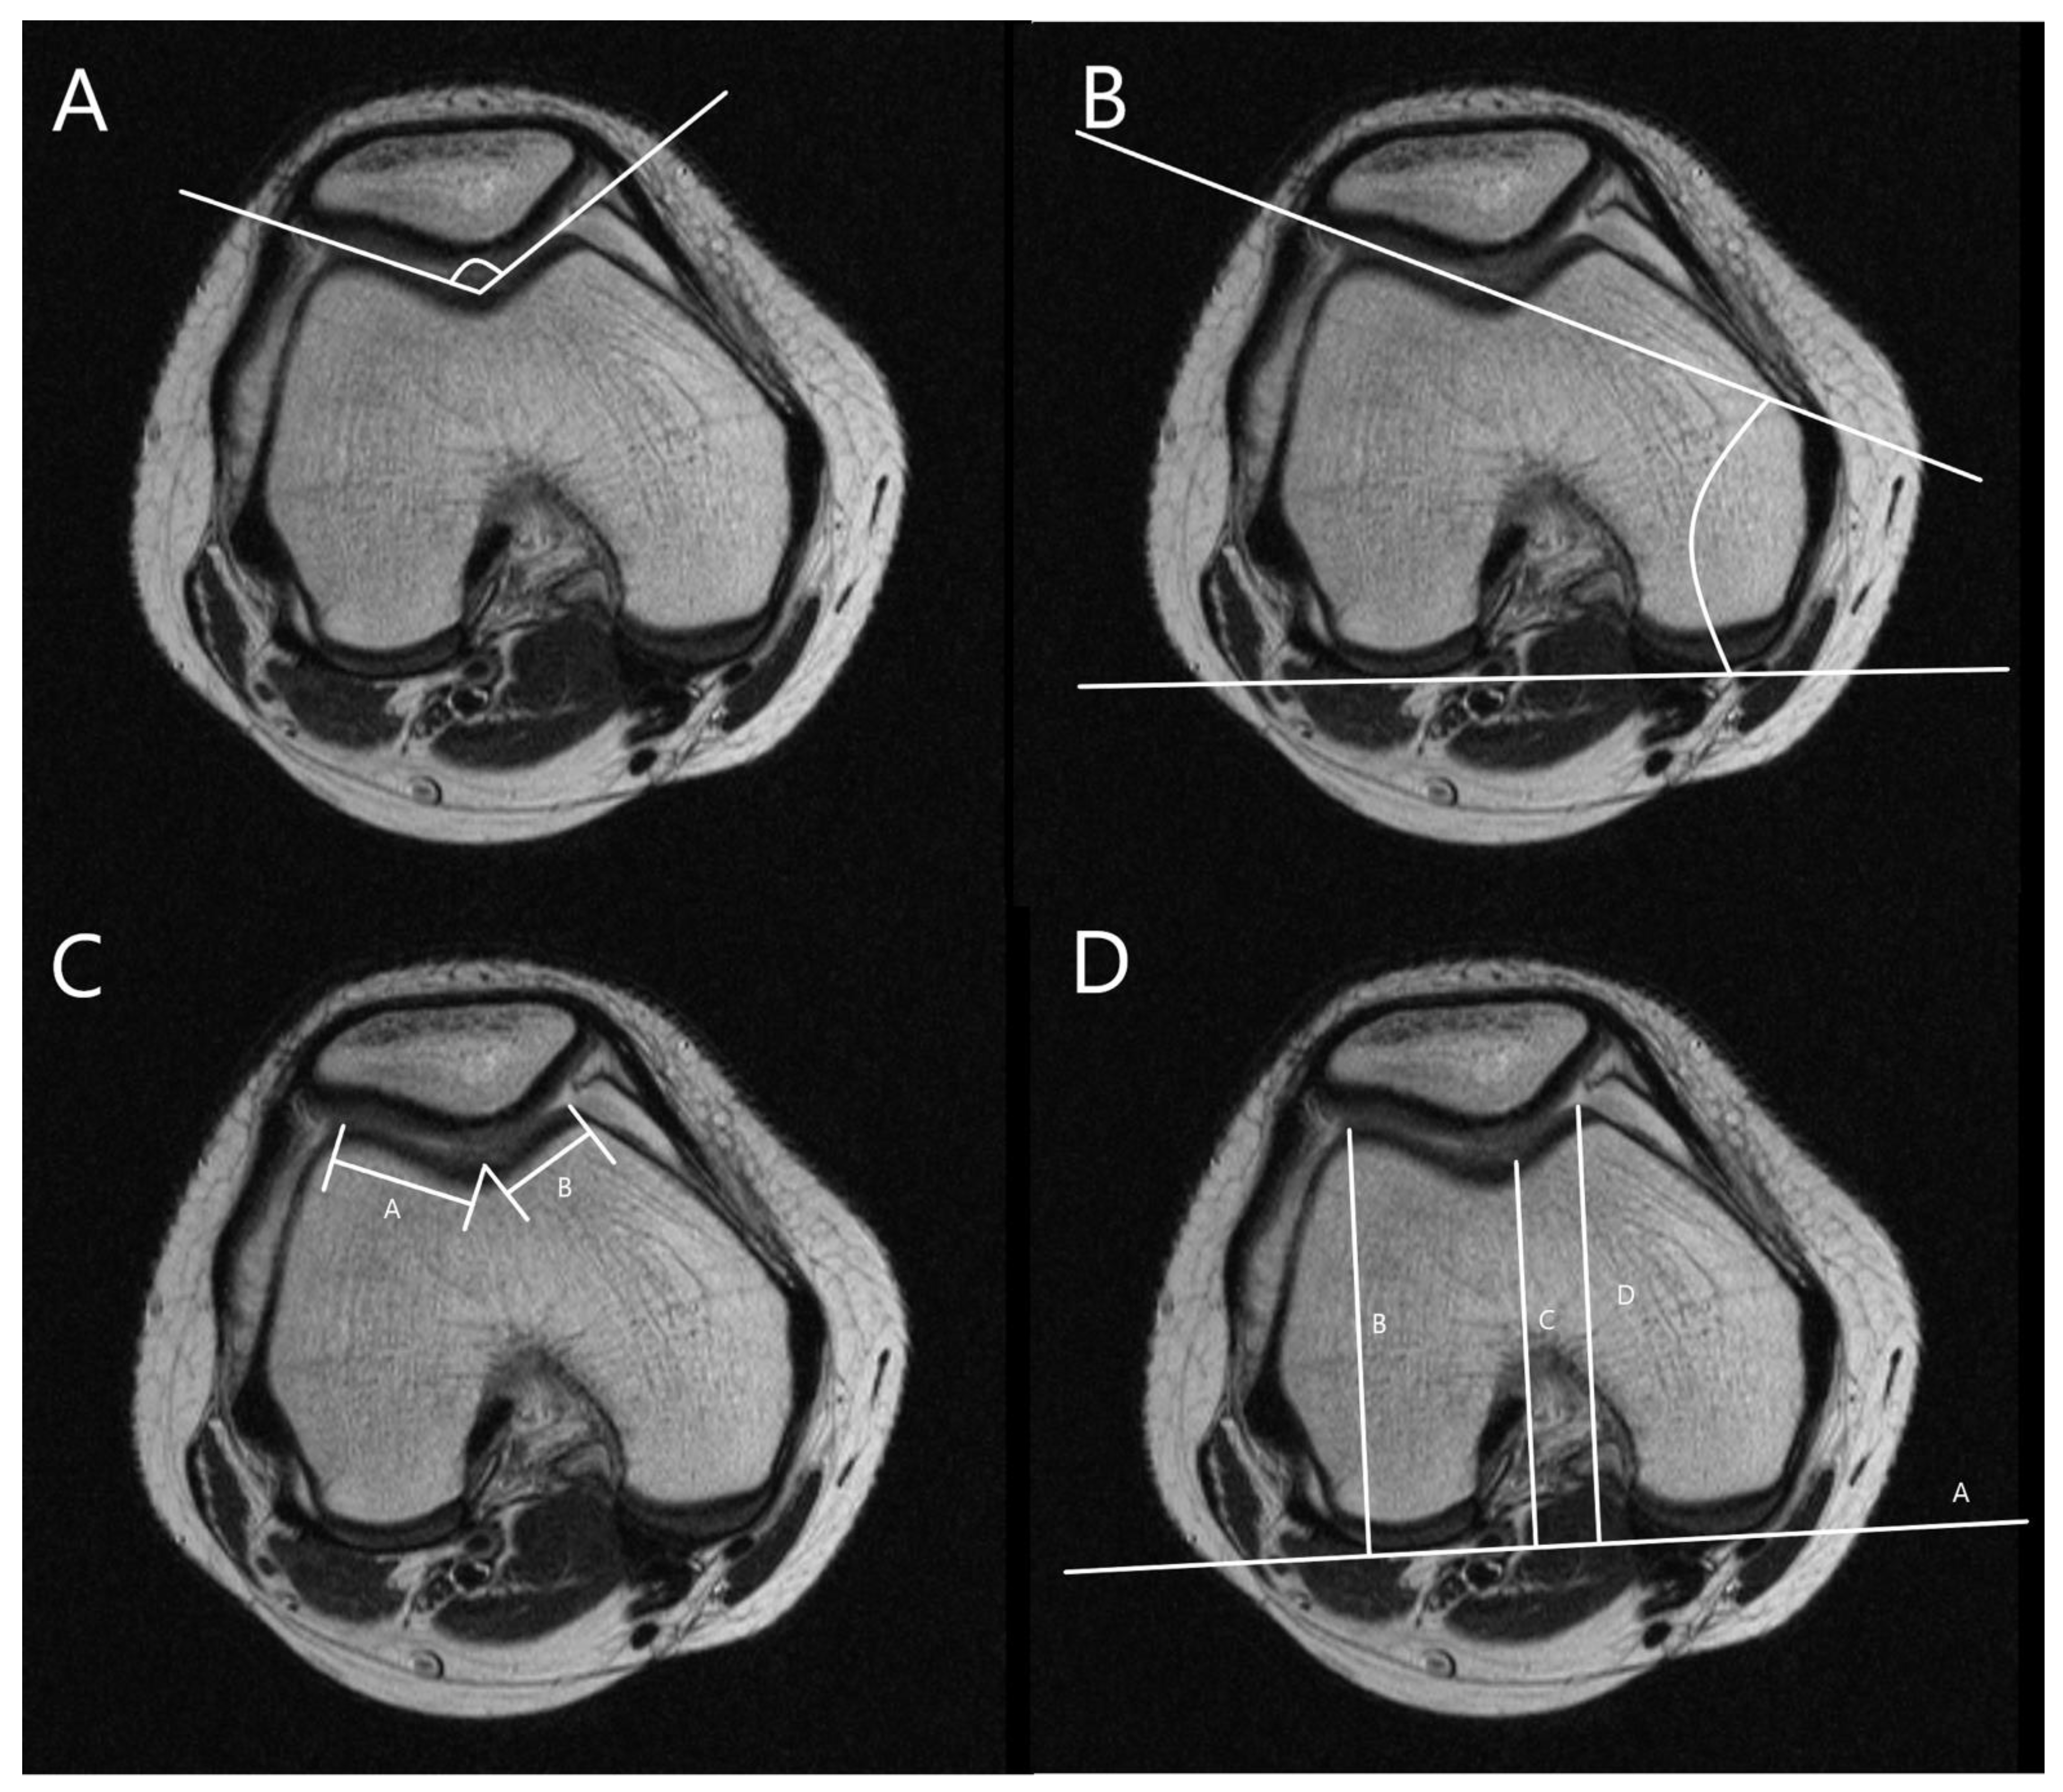

2.2. Radiographic Measurement